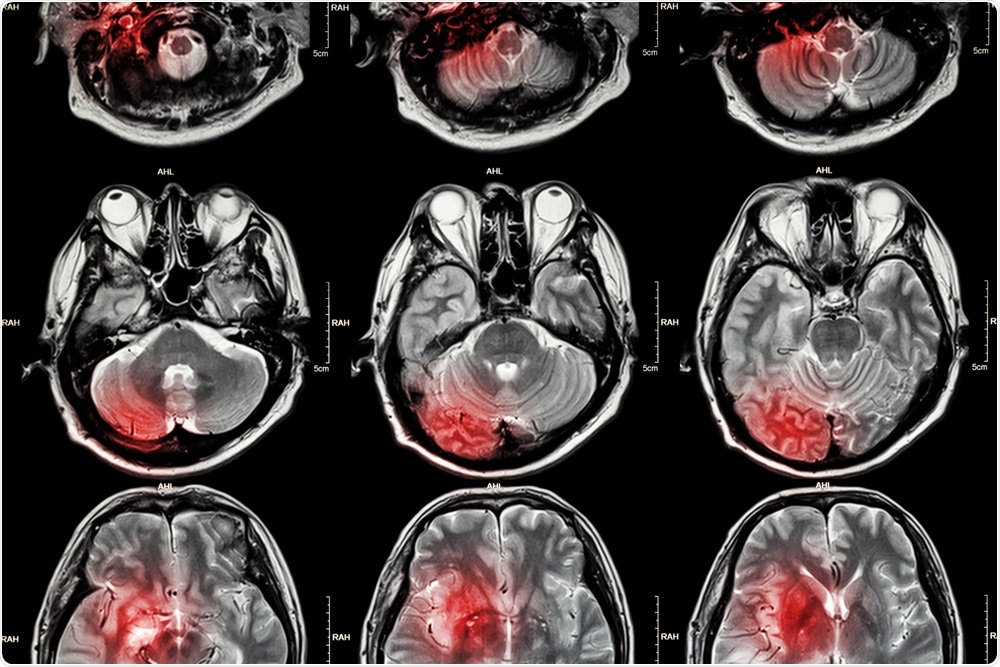

MRI of the brainPuwadol Jaturawutthicha | Shutterstock

For the past decade, MRI (Magnetic Resonance Imaging) has been considered more effective than CT (Computerized Tomography) at diagnosing stroke. Since 2010, medical professionals have been advised to favor MRI in this kind of diagnosis following new guidelines from American Academy of Neurology.

Up until this point, CT scans were the standard test for diagnosis, but it was recognized that with its ability to generate clearer images of brain tissue, MRI was more appropriate for highlighting brain regions where brain damage had occurred due to lack of blood flow resulting in restricted water diffusion through the tissue. MRI has been found to accurately detect stroke 83% of the time, compared with just 26% through CT.